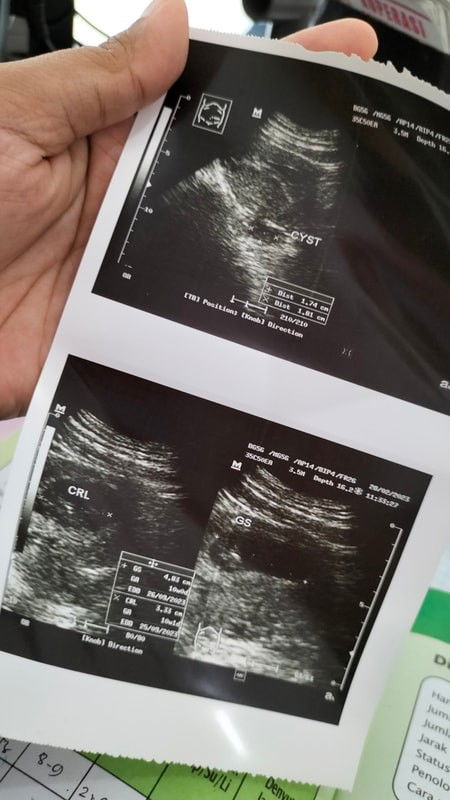

Bun, ini tadi kan aku pertama kali USG setelah usia kehamilan 9week6hari , pas usg tadi uk 10week1hari dan tadi juga baru tau kalau ternyata ada kista untungnya juga kata dokternya ukurannya gak besar dan saya kaget dong terus tanya apakah aman katanya aman gak mengganggu kehamilannya. Nnti kalau sudah melahirkan bisa diambil juga . Tapi saya takut Bun, terus juga dulu sebelum hamil juga kalau mens gak pernah sampai nyeri banget dan gak sering juga. Tapi katanya faktor kista dari mens yang nyeri berlebihan Apa bunda2 disini ada yang ngalamin juga seperti saya ??? Dan bersyukur kandungannya sehat, janin berkembang dgn baik semoga sampai persalinan nnti sehat2. #bantusharing #ingintahu #firstmom